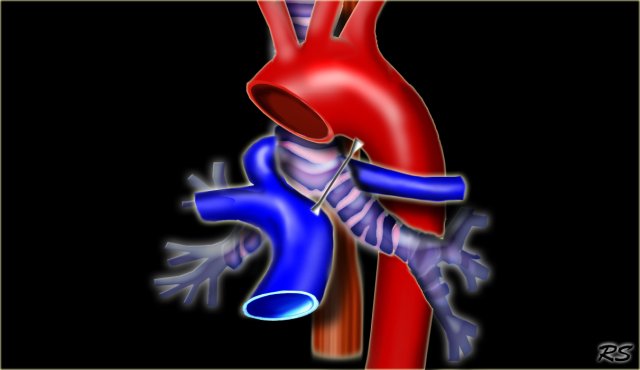

Pulmonary Sling Pulmonary Sling

In pulmonary sling the left PA originates from the right PA and courses between the esophagus and the trachea, where it compresses the right main bronchus.

Pulmonary sling is seen more frequent in children as it is more symptomatic than in adults, because the chest is smaller, but you can also encounter it in adults.